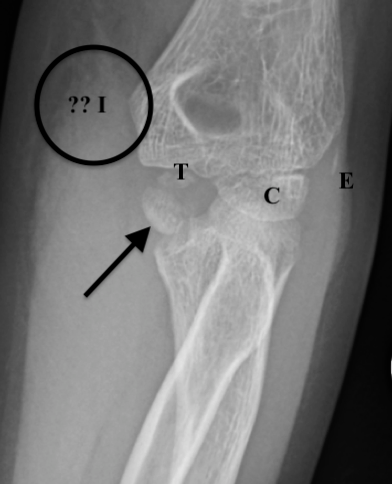

Figure 8B: AP view with markings. Ossification centers of capitellum (C), trochlea (T), and a sliver of external (lateral) epicondyle (E) are seen. The internal (medial) epicondyle (ā€œ?? Iā€ in circle) is missing from its expected location and is identified by the arrow, avulsed into the joint. There is also significant medial soft tissue swelling near the circle.